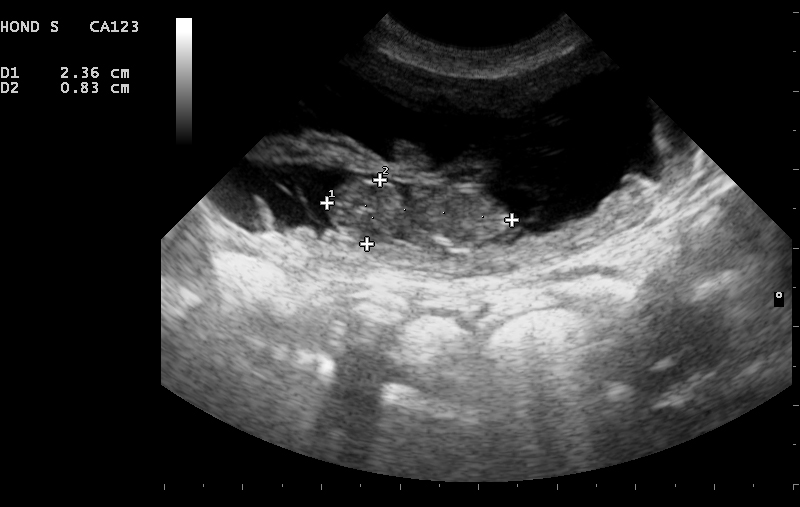

Naast bevestigen van de dracht heeft de echo als voordeel dat het ons meer informatie geeft over de gezondheid van de pups of kittens. Er kan bekeken worden of de dracht normaal verloopt en de hartactie van de foetussen kan bekeken worden. Wanneer het moment van dekken niet bekend is, kan er een schatting gemaakt worden van de drachtduur aan de hand van het formaat van de foetussen. Hiervoor bestaan bepaalde formules, deze zijn zeker niet geheel betrouwbaar maar kunnen een richting geven. Ook kan er een schatting gemaakt worden van het aantal pups of kittens dat verwacht wordt. Het is echter belangrijk om te weten dat dit bij echo nooit met 100% zekerheid kan worden vastgesteld. Tijdens het maken van echo bewegen de foetussen, waardoor ze soms niet of juist dubbel geteld kunnen worden bij het langsgaan van de baarmoederhoorns. Ook is het zo dat hoe verder we in de dracht zitten, des te onbetrouwbaarder wordt het. Dit komt omdat de pups en kittens steeds groter worden, waardoor je meerdere keren hetzelfde pup of kitten kunt tellen.